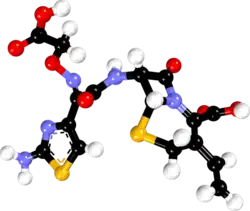

| 3D model (JSmol) | |

| |

| |

| | |